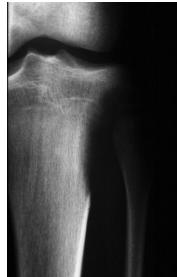

site: Diaphyseal, metaphysal size: partial matrix: Mixed - Narrow zone of transition, well defined, syndosmosis soft tissue involvement: No tissue involvement